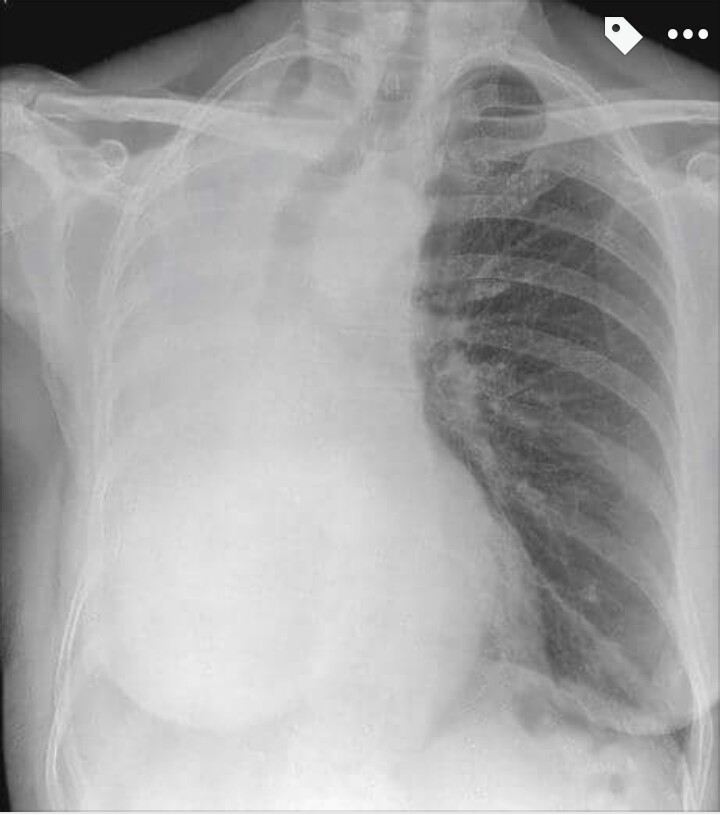

Right Lung Collapse

with deviation of the trachea and complete shift of the mediastinum to the right. The trachea and left main bronchus are visible, but there is an abrupt ‘cut off’ of the proximal right main bronchus. The appearances are of complete collapse of the right lung. CT shows extensive mediastinal and right hilar lymphadenopathy

extent, bronchus intermedius. There is also a moderate right pleural effusion.

IMPORTANT GOLDEN POINT: It is important to recognise the signs that help you determine the cause of complete opacification of a

hemi-thorax. Here, the signs are of complete lung collapse

with mediastinal shift to the abnormal side into the space created by the collapsed lung. There are no signs of previous surgery to suggest that the patient had undergone a pneumonectomy. If the cause was due to a large pleural effusion, there would be mediastinal shift away form the abnormal side due to the mass

effect of the effusion. A large mass together with a moderate effusion may result in central mediastinum.